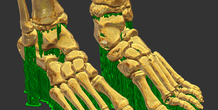

foot bone

by imlab

Bone of human foot that was created from DICOM images. This model has been generated support. Ready to print by 3D printer.